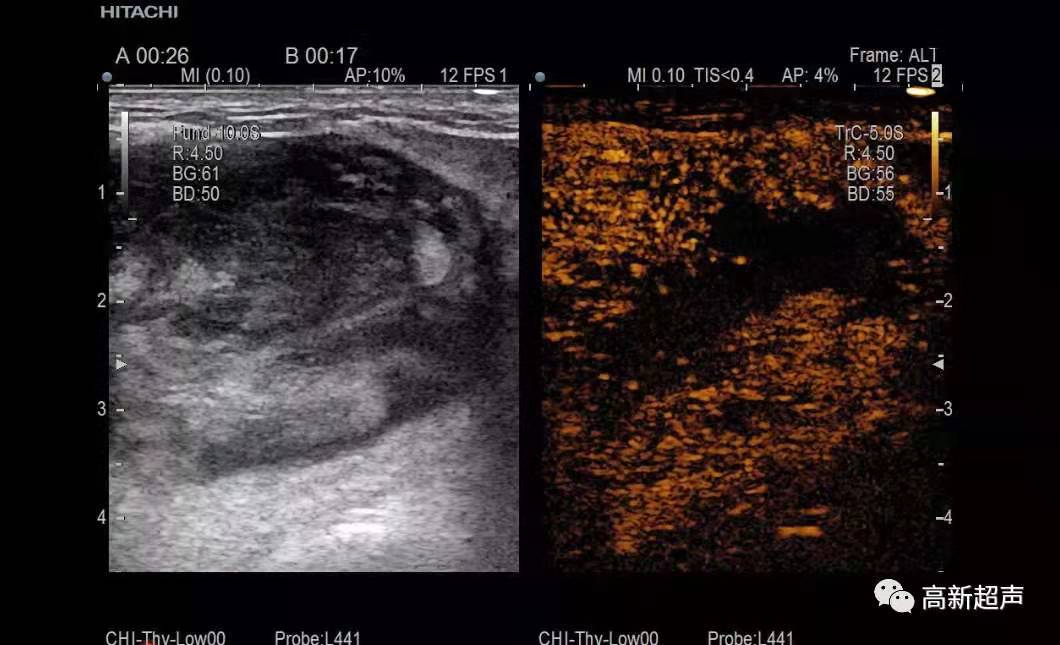

在科主任黃曉新的帶領(lǐng)與支持下,周英華副主任開展了腫瘤的穿刺活檢術(shù),填補(bǔ)了超聲科在此項(xiàng)技術(shù)上的空白。現(xiàn)已成功進(jìn)行了甲狀腺、乳腺及淋巴結(jié)的穿刺活檢,并可在未來進(jìn)一步開展其他各類實(shí)質(zhì)臟器的腫瘤穿刺活檢及消融治療術(shù),為超聲科介入專業(yè)組的建立踏下了堅(jiān)實(shí)的一步,為臨床醫(yī)生及腫瘤患者制定治療最佳方案提供了可靠的病理學(xué)診斷依據(jù)。